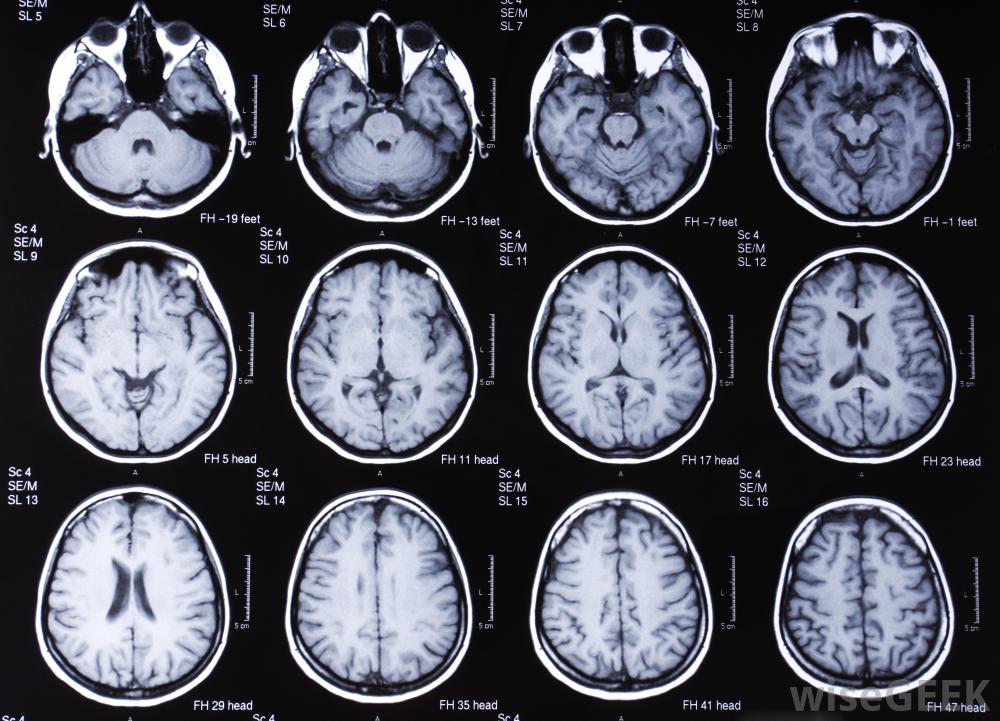

头部的MRI扫描可以帮助诊断慢性硬膜下血肿许多症状都会导致额外的并发症。例如,有这种情况的人可能会有吞咽困难,这可能会导致窒息和误吸四肢无力会导致行动不便,并增加跌倒和进一步受伤的风险。意识混乱和精神状态改变会导致判断能力差,增加受伤和决策失误的风险。慢性硬膜下血肿需要外科手术治疗,并且无法自行愈合,因为血液的采集无处可去。治疗这种情况的程序被称为开颅手术。这个过程包括在头骨上开一个小洞,排出积聚的血液。手术和未经治疗的情况都有永久性脑损伤的风险,但慢性硬脑膜下血肿未经治疗的风险要大得多。慢性硬膜下血肿通常是由头部外伤引起的,60岁以上的人更容易发生。作为自然衰老过程的一部分,大脑可能会萎缩或者萎缩,意味着大脑表面变小,硬脑膜和脑表面之间的间隙变大,然后桥静脉被拉紧,受到更大的力,即使是轻微的头部外伤,也会造成更大的渗漏和血肿形成的威胁服用抗凝血药物的人患慢性硬膜下血肿的风险增加,因为如果桥静脉开始渗漏,血液无法有效地凝结。在婴儿中,硬膜下血肿通常是由创伤或虐待引起的,如婴儿摇晃综合征。其他人发生慢性硬膜下血肿的高风险包括长期酗酒和滥用药物